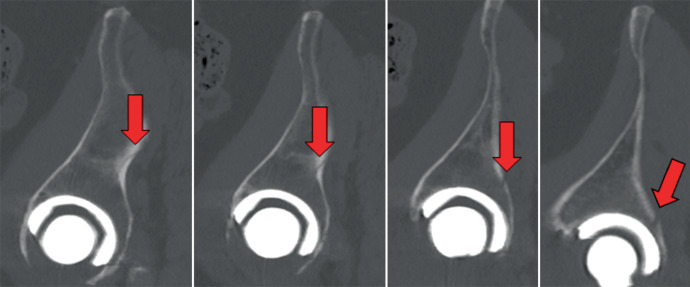

Background: Periprosthetic acetabular fractures primarily pose a problem with cementless implantation techniques and occur in approximately 3.6% of primary and up to 20.9% of revision cases. When a fracture situation exists that affects the integrity of the pelvic columns, stabilization using plate osteosynthesis is necessary, in addition to the implantation of a revision cup. Periprosthetic femoral fractures also primarily occur with cementless techniques and account for 0.4-6.8% of revisions after primary total hip arthroplasty. In addition to the cementless technique, the most common risk factors for the development of PFF are a minimally invasive, ventral approach, female gender, poor bone quality, age > 75 years, and revision surgery.

Treatment: Depending on the degree of risk to the stability of the implant, conservative or surgical treatment can be carried out using osteosynthesis, stem replacement or a combination of both procedures.